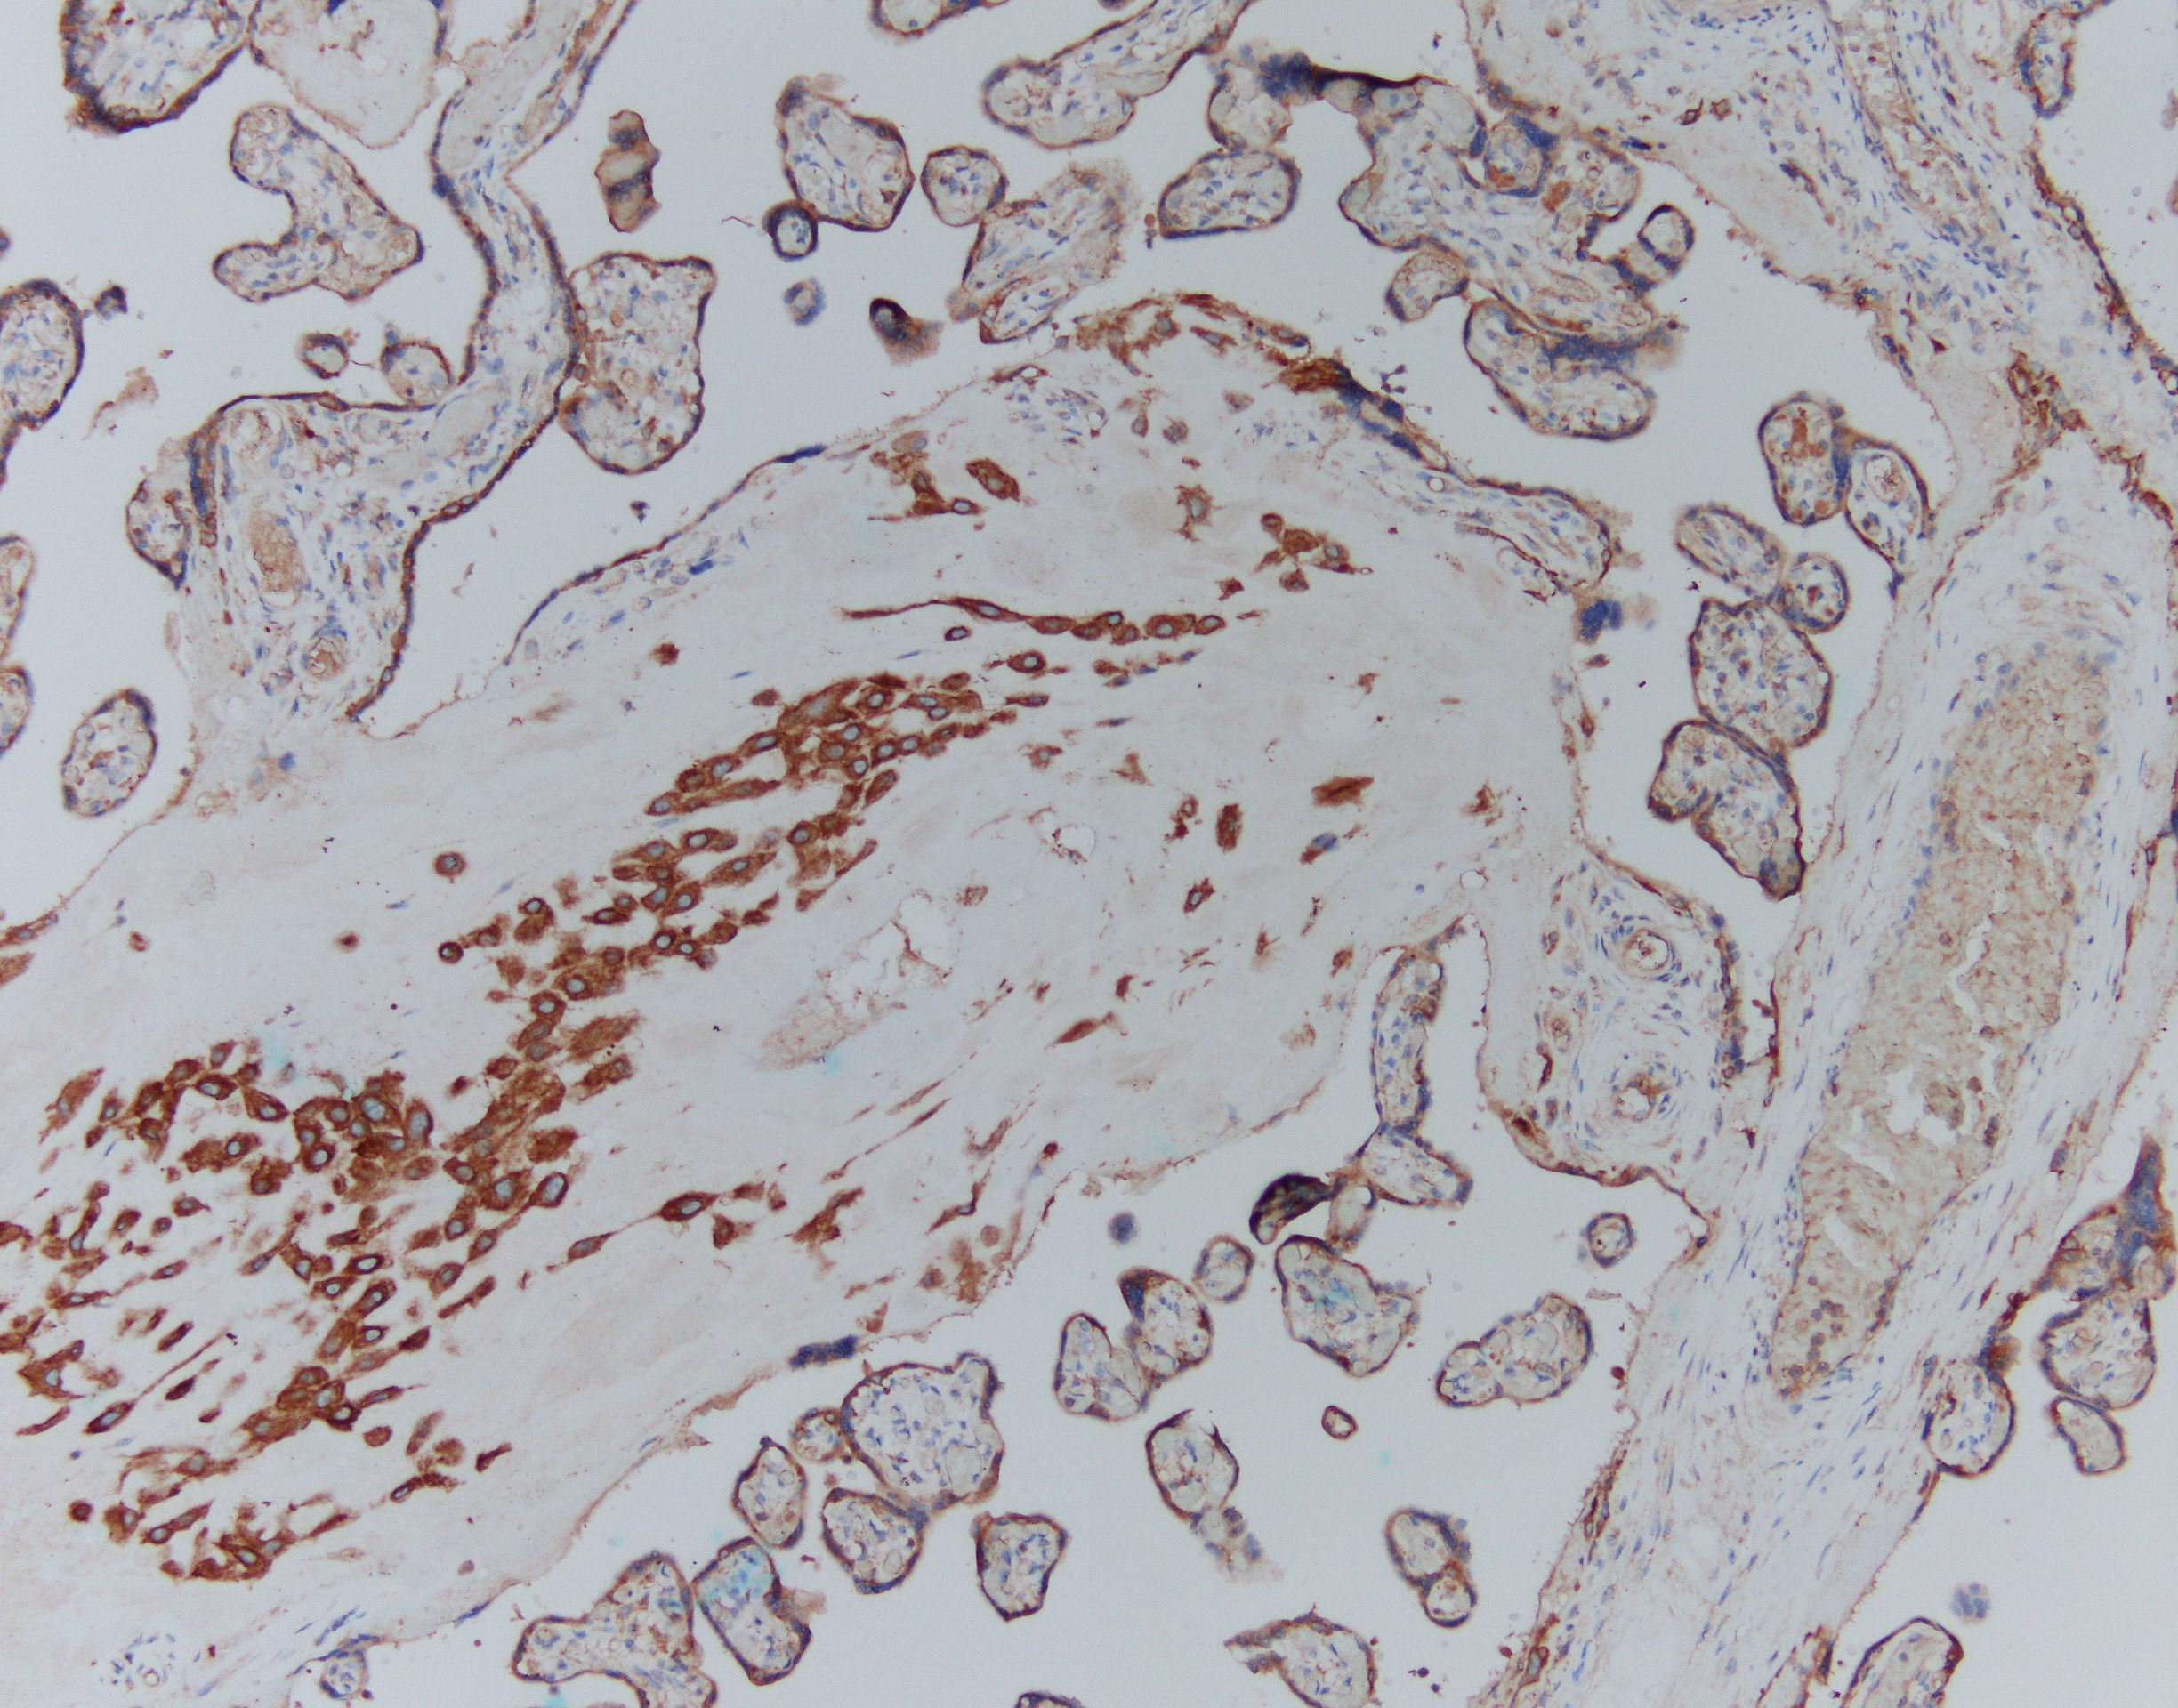

CFTR in Human Placenta. CFTR was detected in immersion fixed paraffin-embedded sections of human placenta using Mouse Anti-Human CFTR R Domain Monoclonal Antibody (Catalog # MAB1660) at 15 µg/mL overnight at 4 °C. Before incubation with the primary antibody tissue was subjected to heat-induced epitope retrieval using Antigen Retrieval Reagent-Basic (Catalog # CTS013). Tissue was stained using the Anti-Mouse HRP-DAB Cell & Tissue Staining Kit (brown; Catalog # CTS002) and counterstained with hematoxylin (blue). Specific labeling was localized to the plasma membrane and cytoplasm of decidual cells. View our protocol for Chromogenic IHC Staining of Paraffin-embedded Tissue Sections.